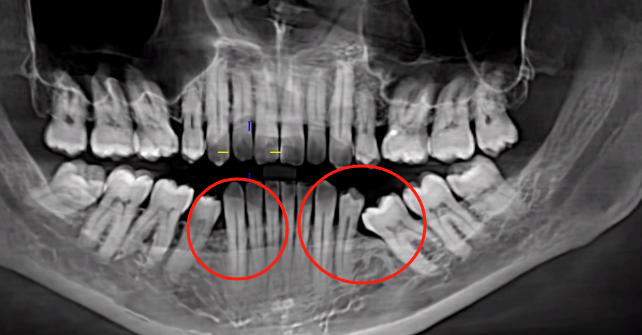

2. Mesial Drift of Adjacent Teeth: Compromising Tooth Longevity and Implant Space

Another critical consequence is the mesial drift (tilting) of adjacent teeth into the edentulous space. Without the physical support of the missing tooth, the neighboring teeth lose their natural occlusal balance, causing them to shift gradually toward the gap. This drift weakens the periodontal ligament and alveolar bone support of the adjacent teeth, accelerating their degradation and reducing their lifespan. More importantly, severe tilting can obliterate the necessary three-dimensional space for implant placement (requiring at least 7–10 mm of mesiodistal width and 12–15 mm of vertical height). Correcting this often necessitates pre-implant orthodontic treatment to upright the tilted teeth, adding months to the treatment timeline and further increasing costs. Untreated, this misalignment can also lead to occlusal disharmony, temporomandibular joint (TMJ) disorders, and uneven wear of opposing teeth.